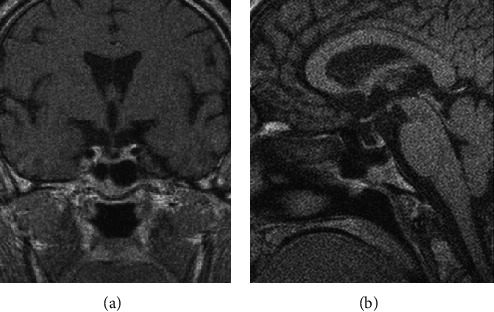

Abstract Image

Acromegaly and gigantism are hormonal disorders which develop as a consequence of chronic growth hormone hypersecretion. The prefix pseudo- is used to describe a certain clinical condition without a clearly proven characteristic of pathophysiological mechanism and basic biochemical features; pseudoacromegaly or acromegaloidism match the definition from above. In this case reports, we will try to provide a concise overview of diagnostic evaluation of acromegaloid physical appearance, while discussing two cases of patients who have similar clinical acromegaloid features as the first sign of the disease but have completely different etiologic backgrounds of their acromegalic appearance. The first case is of a 57-year-old male who presented with a marked acral growth and coarse facial features, but the diagnosis of secondary amyloidosis caused by multiple myeloma was confirmed just after biopsy of tongue and buccal mucosa. The second case is that of a 63-year-old male with an acromegaloid appearance caused by ectopic secretion of GH secreting lung carcinoma. The early diagnosis of ectopic acromegaly and pseudoacromegaly is still a challenging process. The key task is to confirm the GH axis abnormalities and establish the underlying disease, as a crucial step for faster treatment and need to avoid unnecessary therapeutic procedures to decreased mortality and improved quality of life.